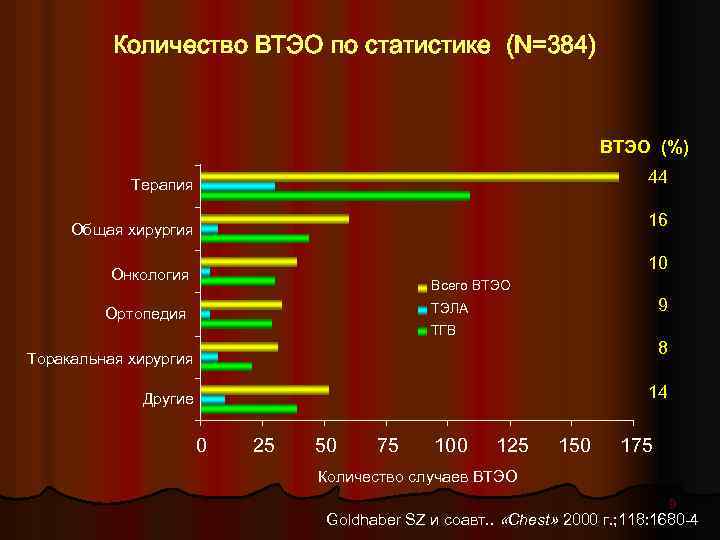

Количество ВТЭО по статистике (N=384) ВТЭО (%) 44 Терапия 16 Общая хирургия 10 Онкология Всего ВТЭО 9 ТЭЛА Ортопедия ТГВ 8 Торакальная хирургия 14 Другие 0 25 50 75 100 125 150 175 Количество случаев ВТЭО 9 Goldhaber SZ и соавт. . «Chest» 2000 г. ; 118: 1680 -4